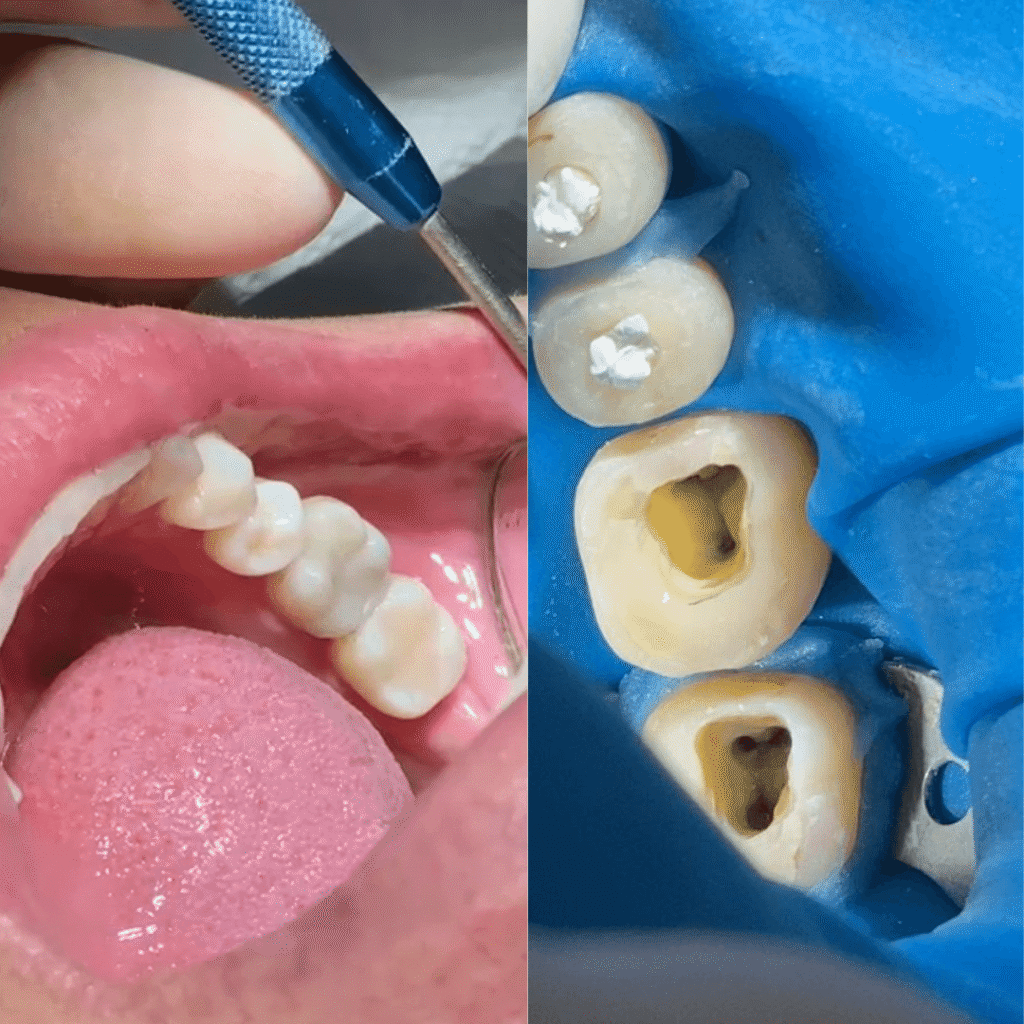

Isolamento do campo operatório, aumentando nosso campo de visão

Uso do raio x digital, permitindo um melhor diagnóstico pro seu caso

Diagnóstico preciso para confirmar a necessidade do canal

Tratamento completo no mesmo consultório: do canal à reconstrução final